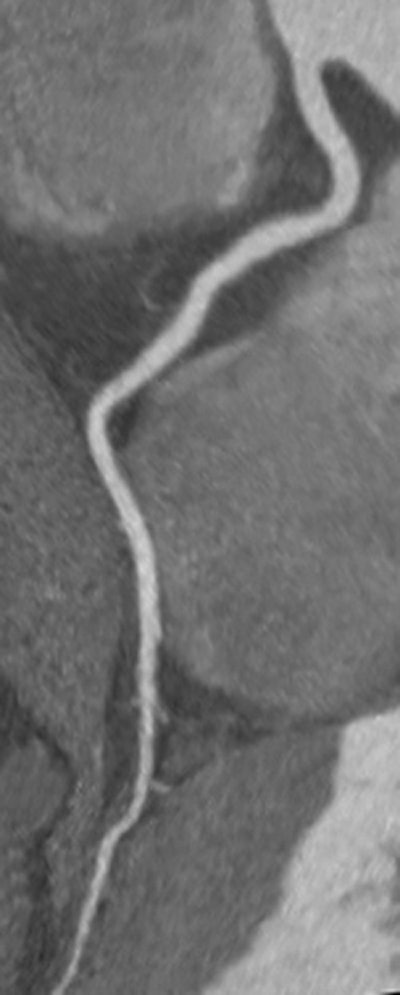

CCTA of a right coronary artery without stenosis or artifacts, imaged with iobitridol 350 mg iodine/mL. Image courtesy of Dr. Stephen Achenbach.

CCTA of a right coronary artery without stenosis or artifacts, imaged with iobitridol 350 mg iodine/mL. Image courtesy of Dr. Stephen Achenbach.The results also indicate iodine content can be reduced further, Achenbach et al wrote. As per common practice, iodine delivery rate was not adjusted, although doing so would have eliminated a key limitation.